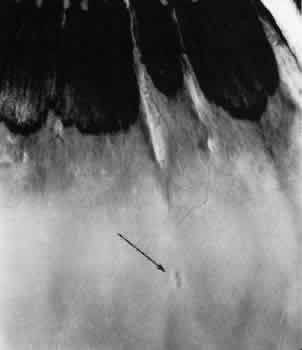

Fig. 13. Meridional complexes with peripheral retinal excavation. Two complexes can be seen anteriorly; both contain meridional folds (the fold of complex on the right is discontinuous). Peripheral retinal excavation (arrow) is aligned with the complex on the left (× 12.)